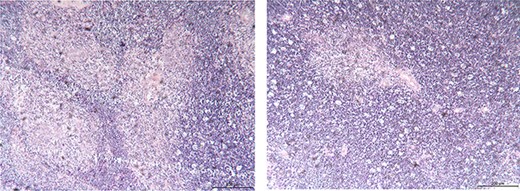

A 39-year-old Chinese female was diagnosed with a pituitary tumor at age 18 when she noticed aberrant growth development. Throughout the years, she developed PHPT, gastrinoma and bilateral adrenal hyperplasia. She was referred to our hospital for further evaluation to confirm the diagnosis of MEN1. Enhanced computed tomography (CT) demonstrated a 7.8-cm by 3.5-cm irregular anterior mediastinal solid-cystic mass within the thymic region (Fig. 1). The lesion was highly suspicious for thymic neoplasm radiologically. The patient subsequently underwent a video-assisted thoracoscopic thymectomy under general anesthesia. No tumor invasion to the pericardium and lung was observed, and the tumor was completely removed. Histopathology examination revealed WHO Type AB thymoma (Masaoka Stage I) (Fig. 2). Following surgery, annual screening showed no evidence of local recurrence or distant metastasis.

Histological findings of the surgical specimens; thymoma; (hematoxylin–eosin stain; original magnification ×100).